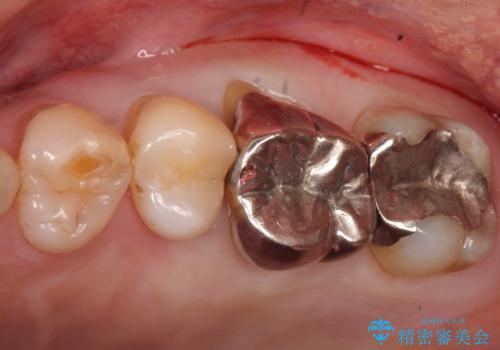

- 奥歯が咬むと痛い、熱いものがしみることを主訴に来院された患者様です。

奥歯(左上7)のメタルインレー(銀の詰め物)を除去し精査したところ、奥歯はわれていました。

根尖近くまで深くヒビが入っており保存不可能な状態でした。